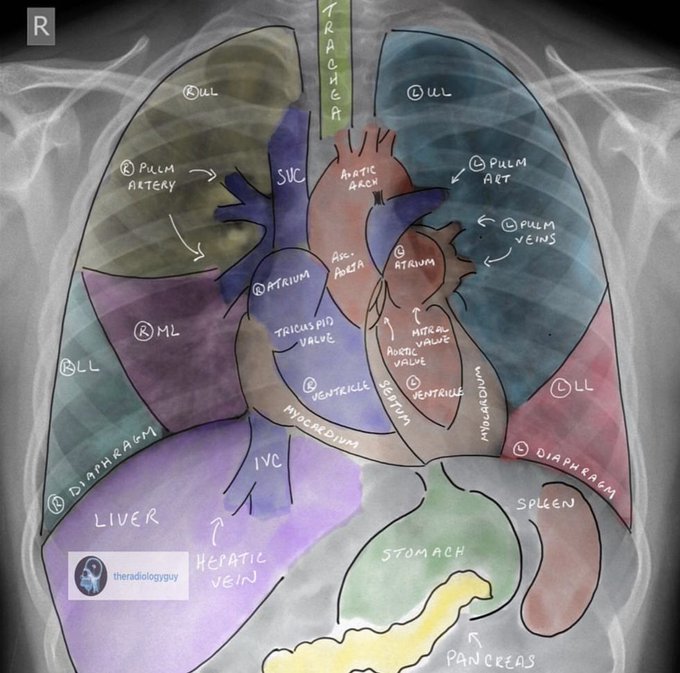

Great image of chest x-ray #anatomy. It amazes me how much imaging we do in #cardiology. Tip! To be a great #interventionalist you gotta master your anatomy and be a pro at imaging! Another amazing overlay by @TheRadiologyGuy ! #cardiotwitter #radiology #meded #foamed #imaging pic.twitter.com/LOmYNLM2aM